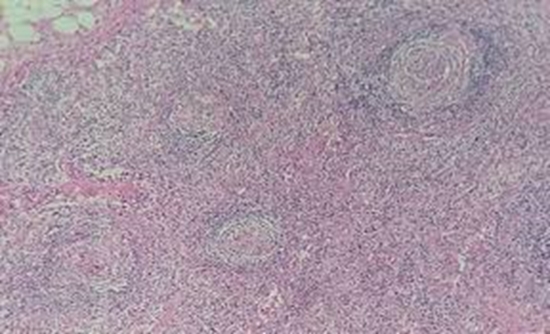

Castleman’s disease (CD) is characterized by non-neoplastic lymph node hyperplasia, and may be localized in a single lymph node (unicentric) or occurs systemically (multicentric). Nowadays, multicentric CD is most commonly observed in individuals infected with human immunodeficiency virus (HIV) type 1, in association with Kaposi’s sarcoma. Histopathologic and immunohistochemical evaluation of excised lymph node as well as imaging modalities, such as computed tomography (CT) and magnetic resonance imaging, are required for the diagnosis of CD.

We present a case of 46-year-old HIV-infected woman with fever, weakness, weight loss, and splenomegaly in the past 18 months. On physical examination, pale conjunctiva, jaundice, multiple cervical, inguinal, and axillary lymphadenopathies as well as hepatosplenomegaly were detected. Chest CT scan showed alveolar opacity in the lower lobe of the right lung and multiple lymph nodes in the mediastinum and bilateral perivascular, cervical, and axillary areas. Abdominopelvic CT scan showed huge splenomegaly, hepatomegaly, and multiple bilateral para-aortic, celiac, and inguinal lymphadenopathies, which were further confirmed as CD in pathological examination.

Huge splenomegaly is a rare manifestation in CD. Among the more prevalent differential diagnoses, CD in patients with HIV and huge splenomegaly was emphasized as important differential diagnosis.